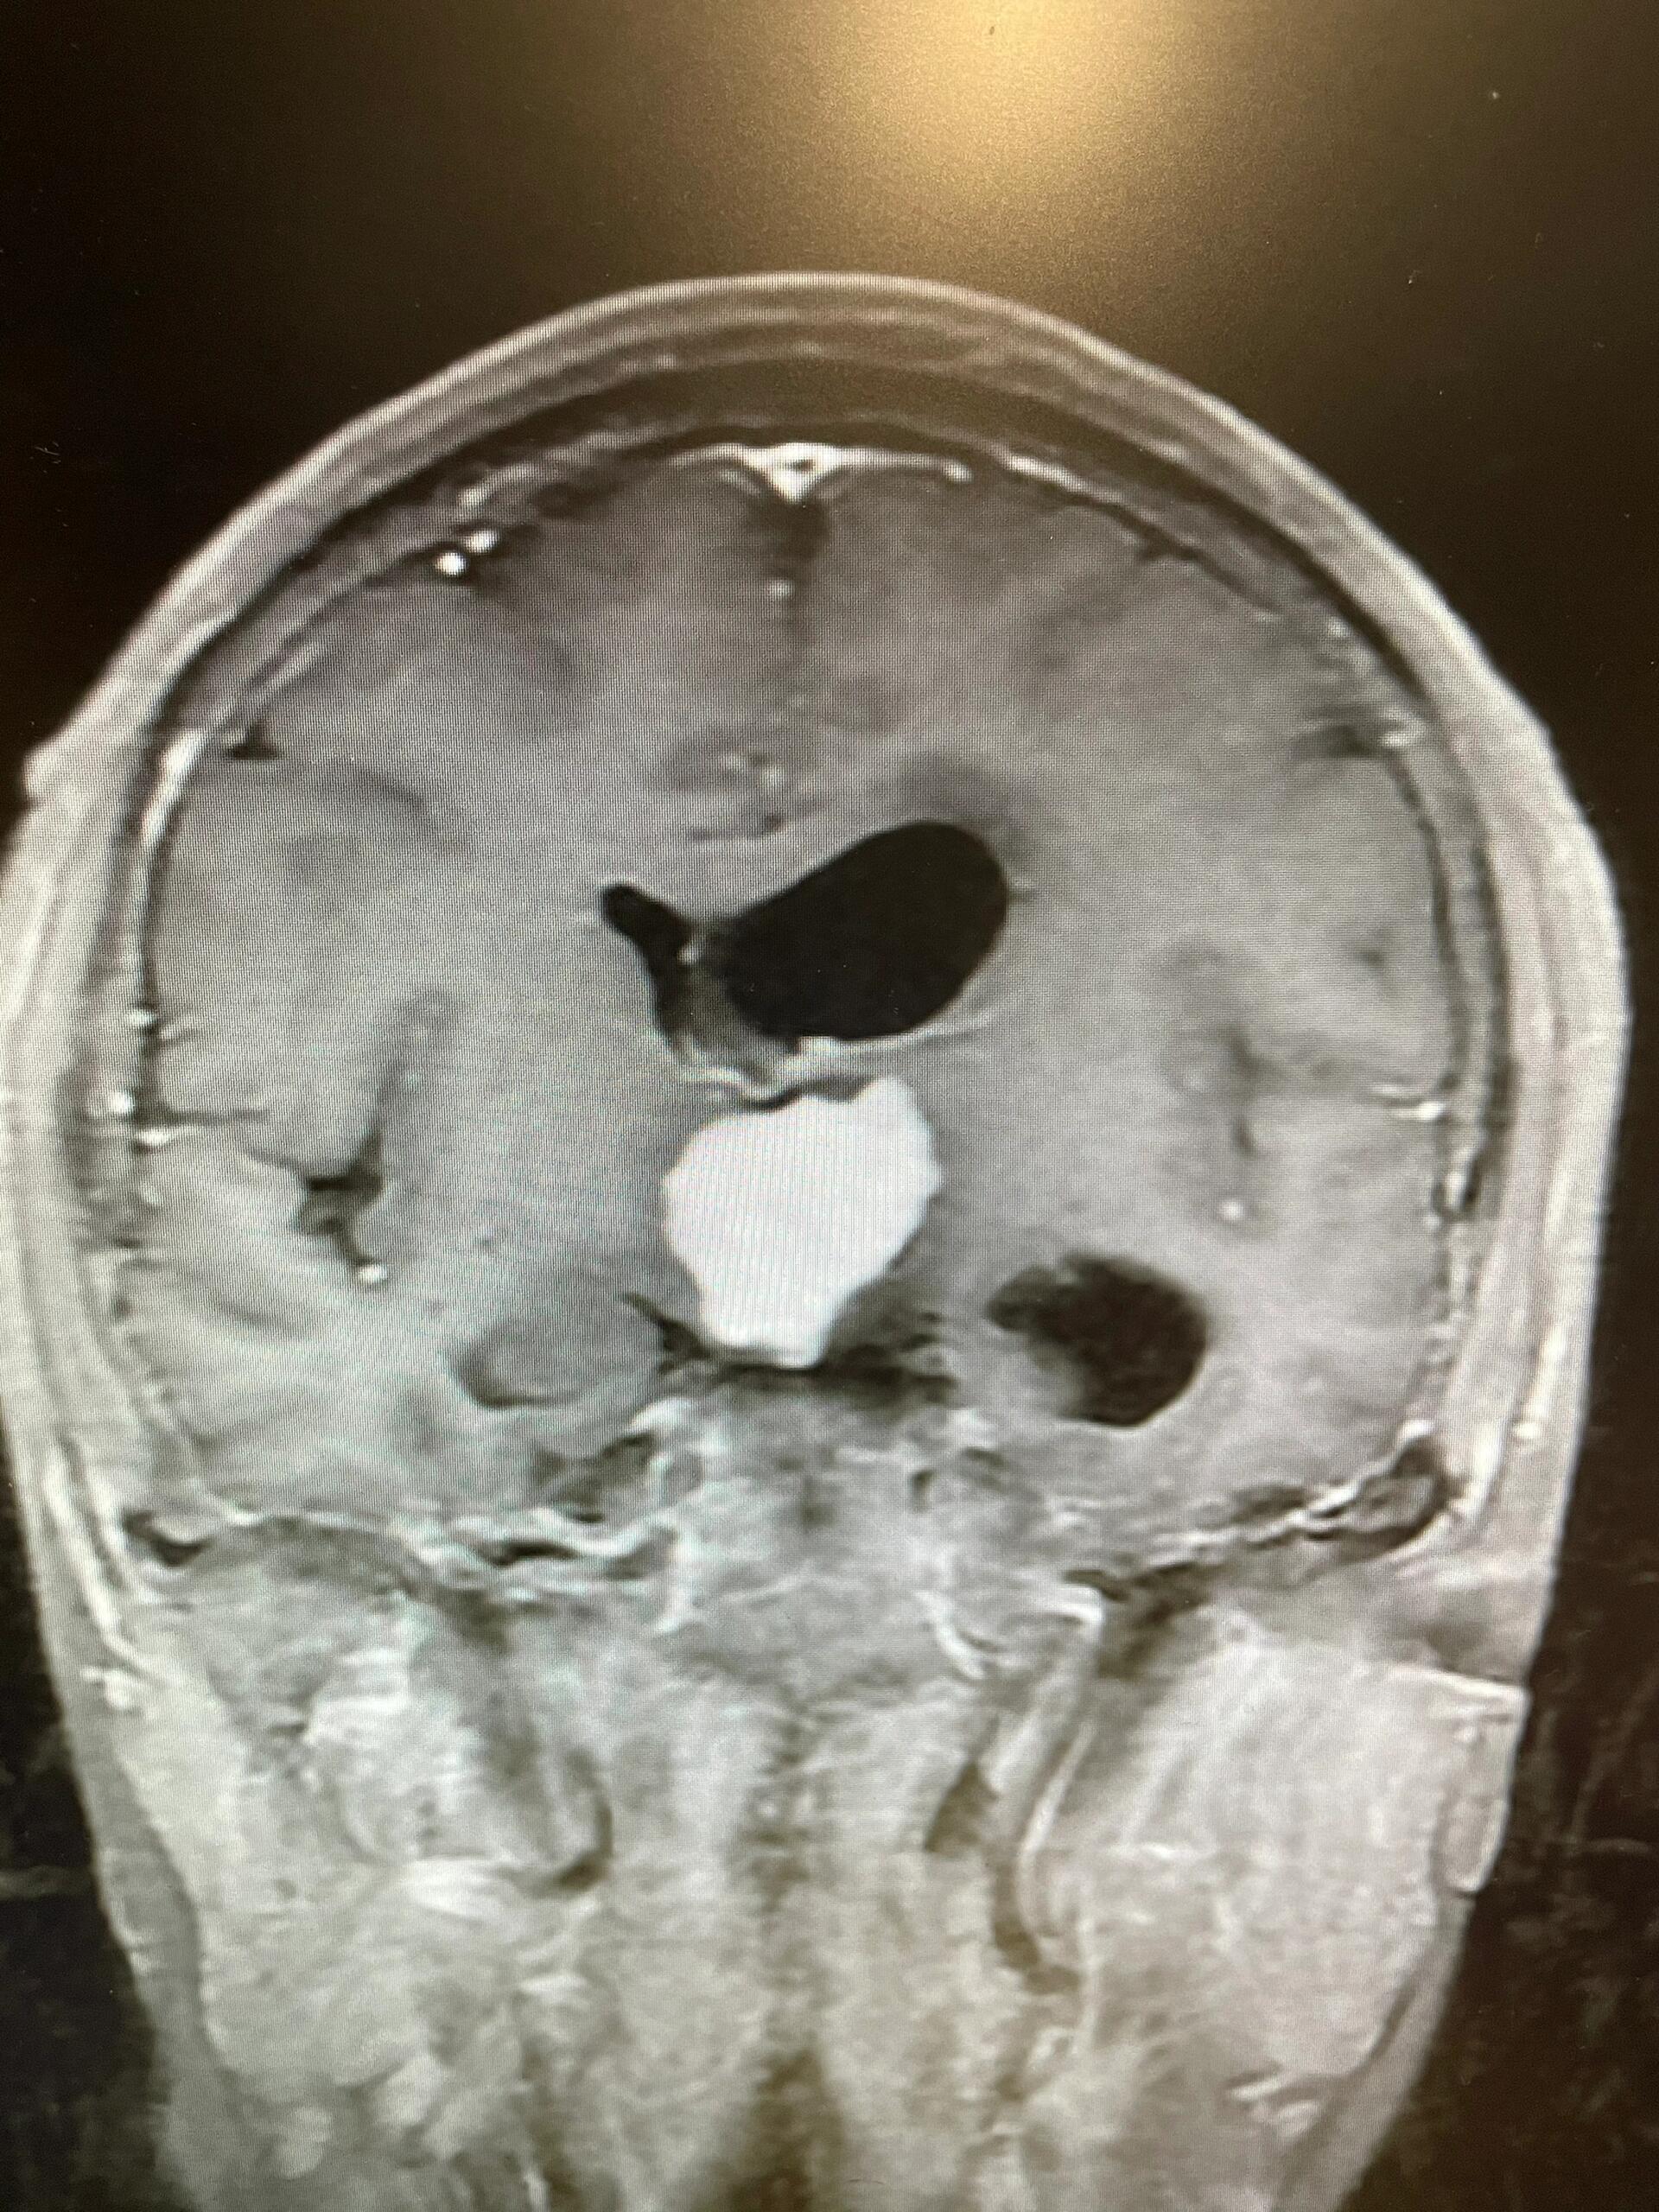

高难度胶质瘤 2024愿每个病人都手术顺利 中年女性,检查发现鞍区肿瘤6

图片尺寸1920x2560